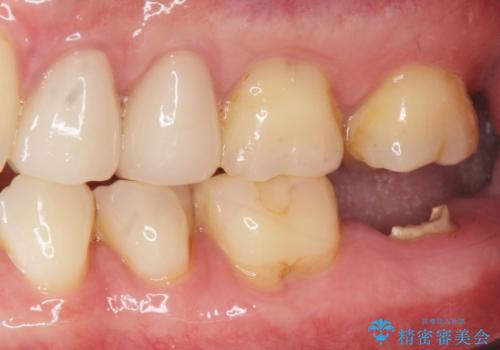

歯からの異臭 虫歯の再発からのインプラント治療

- 「歯から異臭がする。」とのことで相談に来院されました。

X線検査を行ったところ、セラミッククラウン下に虫歯が再発し、歯の破折も認めました。

歯の抜去を行い、骨の造成を含めたインプラントによる咬合機能の回復を図ります。

X線を撮ることで、外から見てもわからない、歯の問題点をより正確に把握することができます。